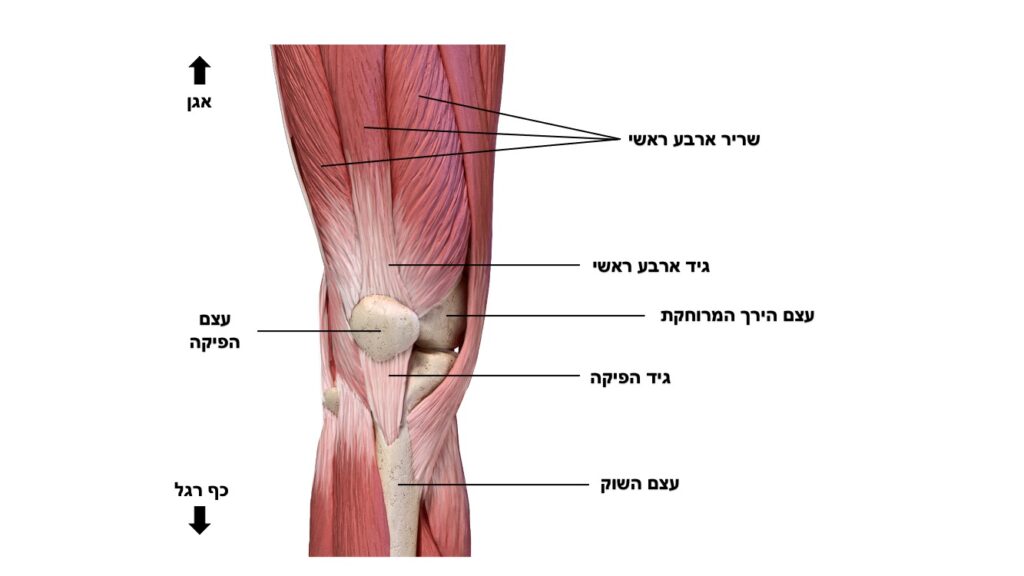

אנטומיה

הפיקה היא עצם השוכנת בתוך הגיד של השריר הארבע ראשי בקדמת הברך. היא מחוברת לרקמות חיבור שונות המייצבות אותה מכיוונים שונים. הפיקה נעה בזמן יישור וכיפוף במגרעת יעודית עבורה בעצם הירך המרוחקת (טרוכלאה). תנועת ההחלקה במגרעת מתאפשרת בזכות רקמת סחוס חלקה אשר עוטפת את הפיקה ואת הטרוכלאה. תפקידה העיקרי של הפיקה הוא תפקיד ביומכני המגדיל את מנוף העבודה של המנגון המיישר של הברך ומעלה את הכח שיכול לייצר השריר הארבע ראשי. תנועה לא תקינה של הפיקה עלולה לגרום לעומסים אבנורמלים באזור זה בברך.